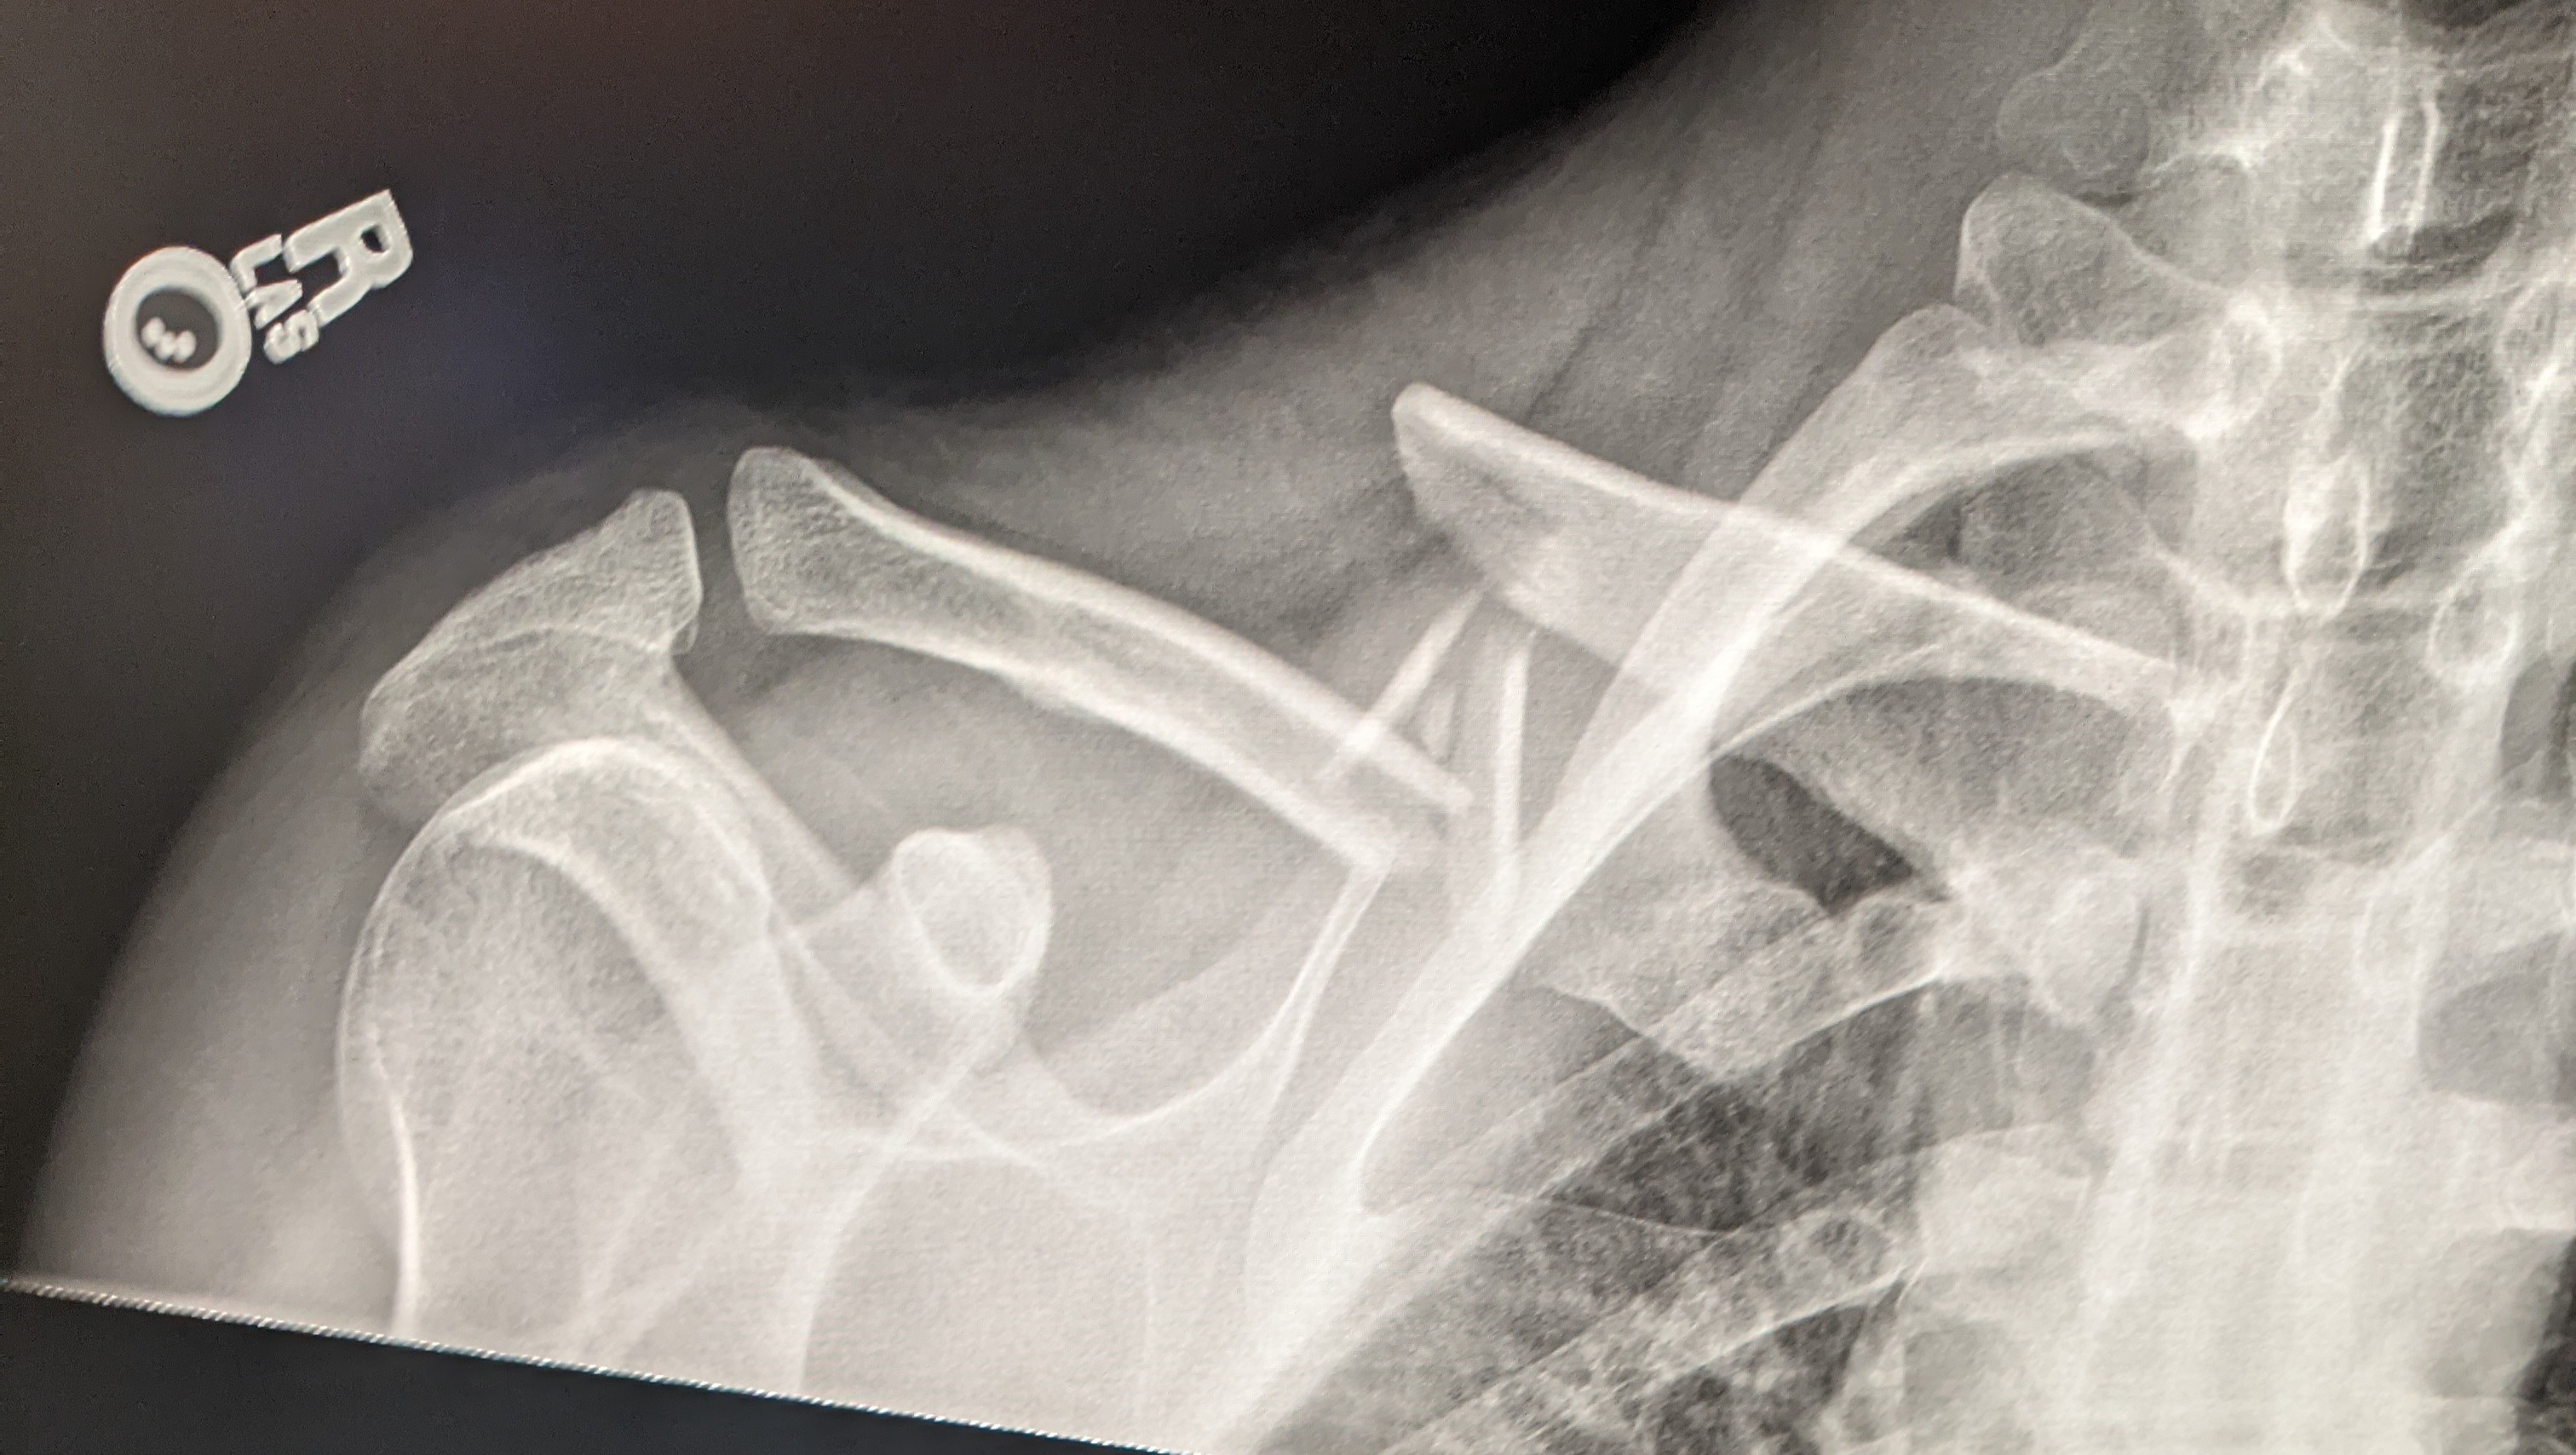

In March 2021 I broke my collarbone while snowboarding. I smashed my whole body against a cliff face. I believe that is when the disc fractured and knocked my hips out of alignment. I then received surgery on my collarbone and sat on the couch for 2 months healing. Meanwhile; my back condition worsened but I was unaware. When the pain from surgery subsided, my back started hurting but I just jumped right into work. The chiro made it worse at that point and I couldn't stretch because it hurt so badly. Then I just kept working and dancing it off. By July I couldn't tie my left shoe normally because I couldn't bend in that way. Then I kept travelling and working festivals and dancing and just ignored it, full denial. Too many awesome things to do.

Collarbone break

Collarbone Surgery